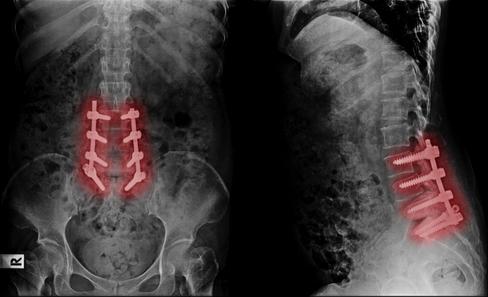

a s ou d ot ea us o , screw and lengthy recoveries. Regenerative Medicine is changing how back pain is solv

Back Pain should not mean fusion, screws, and lengthy recoveries Regenerative Medicine is changing

Back Pain should not mean fusion, screws, and lengthy recoveries Regenerative Medicine is changing how back pain is solved.

Back Pain should not mean fusion, screws, and lengthy recoveries. Regenerative ng how back pain is solved